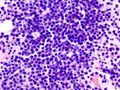

| Micrograph of a plasmacytoma. H&E stain | |

Bone marrow aspirate showing the histologic correlate of multiple myeloma under the microscope. H&E stain.